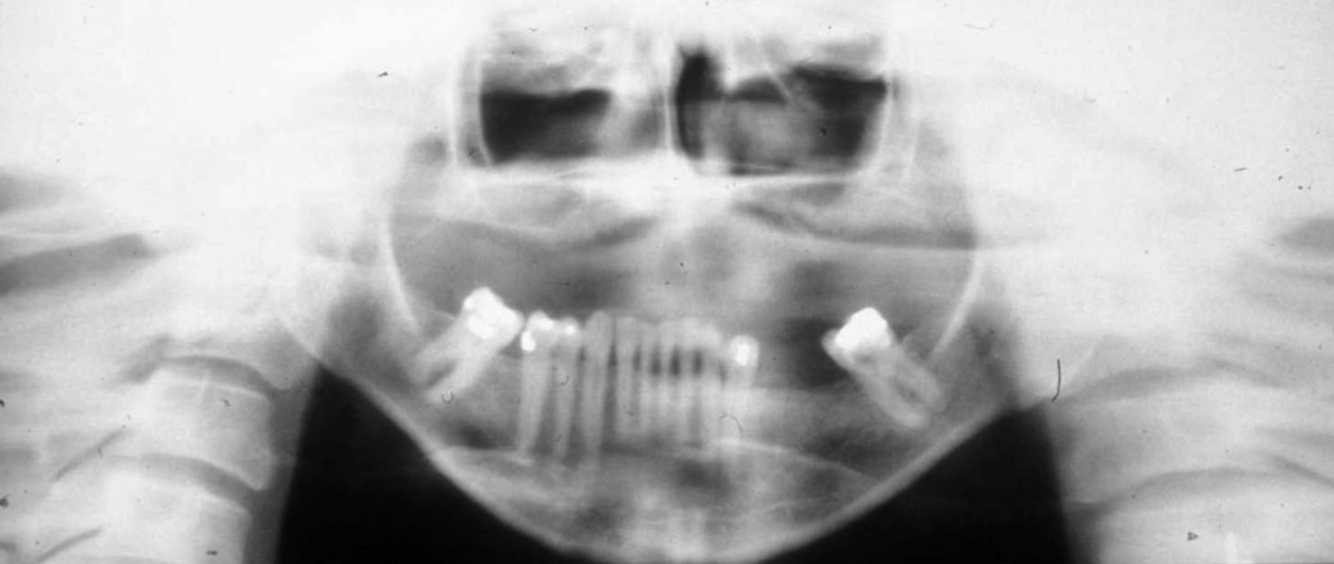

What error is seen in this pano?

A

glasses left on